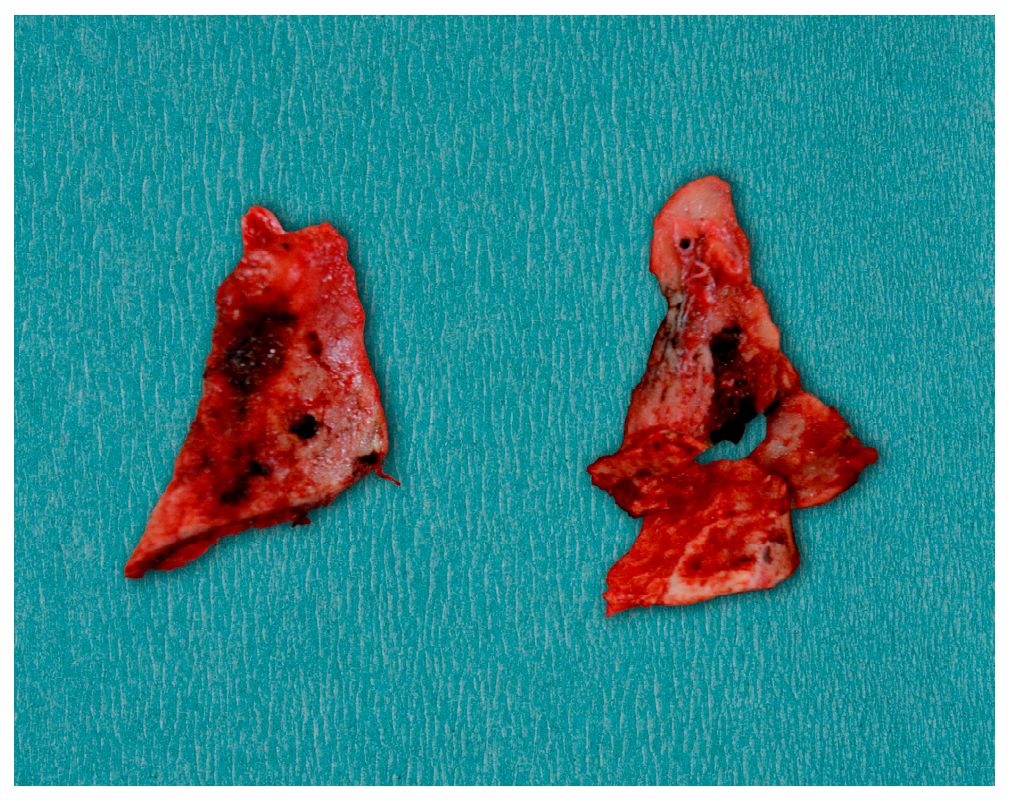

- Case 2

- Case 3